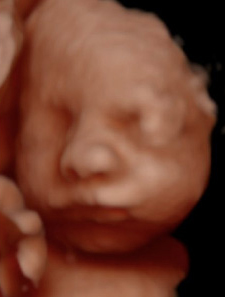

Experimenta la última tecnología hiperrealista 8K, una imagen increíblemente detallada y realista de los rasgos de tu bebé, con una textura y definición que te sorprenderán.

Un recuerdo para toda la vida.

Ecox Alicante ya cuenta con la posibilidad de ofrecer a todos los futuros papis madrileños una experiencia inolvidable gracias a la ecografía 5D y el novedoso hiperrealismo 8K.

Esta nueva tecnología nos permite ofreceros a los futuros papás las imágenes de mayor calidad para que disfrutéis de la experiencia como nunca antes había sido posible.